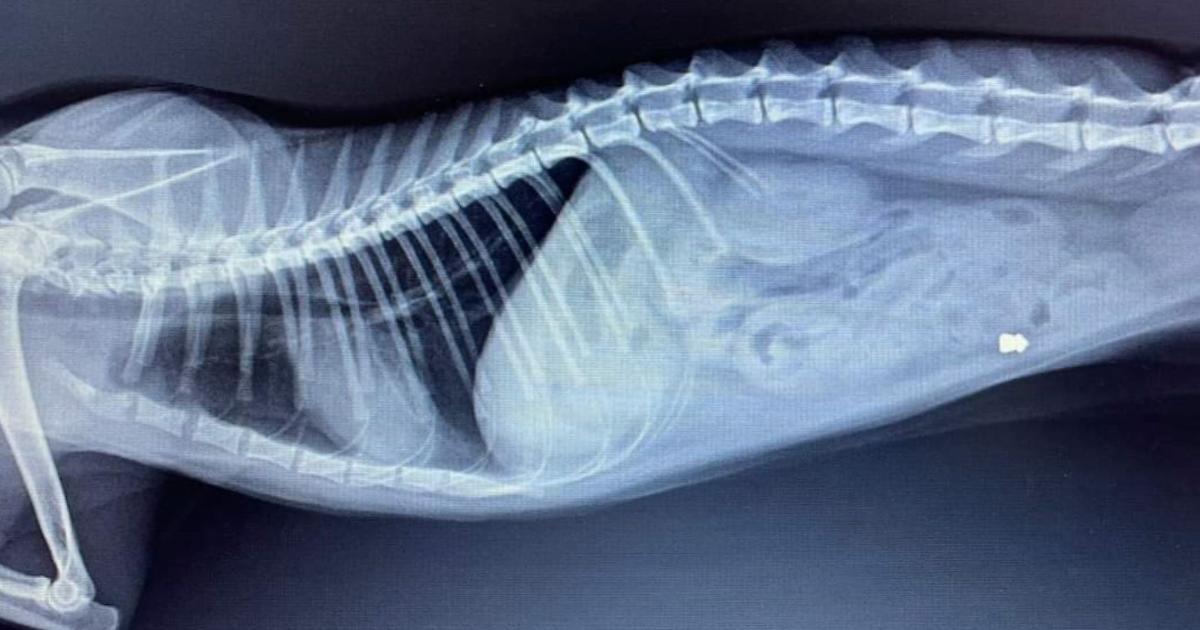

La radiografia di Oscar, colpito con una fucilata

"Chiunque abbia visto o sappia qualcosa si faccia avanti e denunci quanto accaduto contattando il numero 392.272.83.33". L'Ente nazionale protezione animali invita i cittadini a parlare qualora sappiano chi ha sparato ad Oscar, il gatto ferito con un colpo di carabina ad aria compressa a San Giustino Valdarno, in provincia di Arezzo. "Grazie all'amore della sua famiglia e alle cure veterinarie - scrive l'Enpa in una nota - Oscar sta lottando per riprendersi, ma l'indignazione per l’accaduto è enorme. La sezione locale dell’Enpa di San Giovanni Valdarno ha già sporto denuncia contro ignoti e invita" chi sa a farsi avanti. "È inaccettabile - si legge ancora - che nel 2024 episodi di violenza così efferata contro animali indifesi continuino a ripetersi".